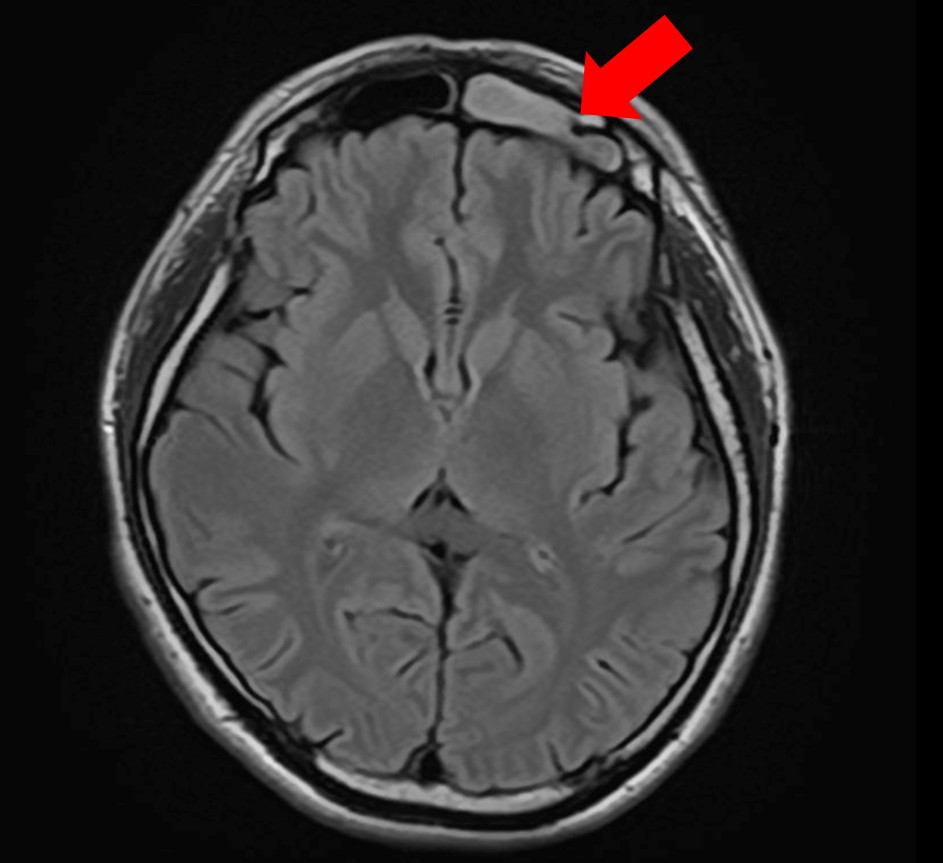

4.【画像解説】MRIでわかる副鼻腔炎と脳の状態

当院では、頭痛の原因を特定するためにMRI検査を実施しています。

正常 副鼻腔 MRI

正常な上顎洞

副鼻腔炎MRI画像

膿がたまっている上顎洞

目の下・周囲の痛みの原因

正常な前頭洞

膿がたまっている前頭同

眉間の痛みの原因

MRI検査の最大のメリットは、「鼻が原因の頭痛」と「脳疾患が原因の頭痛」を一度の検査で同時に、かつ詳細に判別できる点にあります。

【MRIでどこを見るのか】

MRI画像では、脳や脳血管はもちろん、鼻の奥にある空洞を精査します。

健康な状態: 空気が入っているため、炭のように「真っ黒」に映ります。

副鼻腔炎の状態: 膿や粘膜の腫れがある部分は、「白く濁った雲」のように映し出されます。